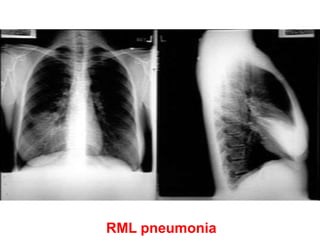

Pneumonia (consolidation) of the right

middle lobe

• CXR PA view showing opacification beneath

the horizontal fissure and loss of normal

contrast between the right heart border and

lung. Suggestive of Rt sided consolidation.

RML pneumonia